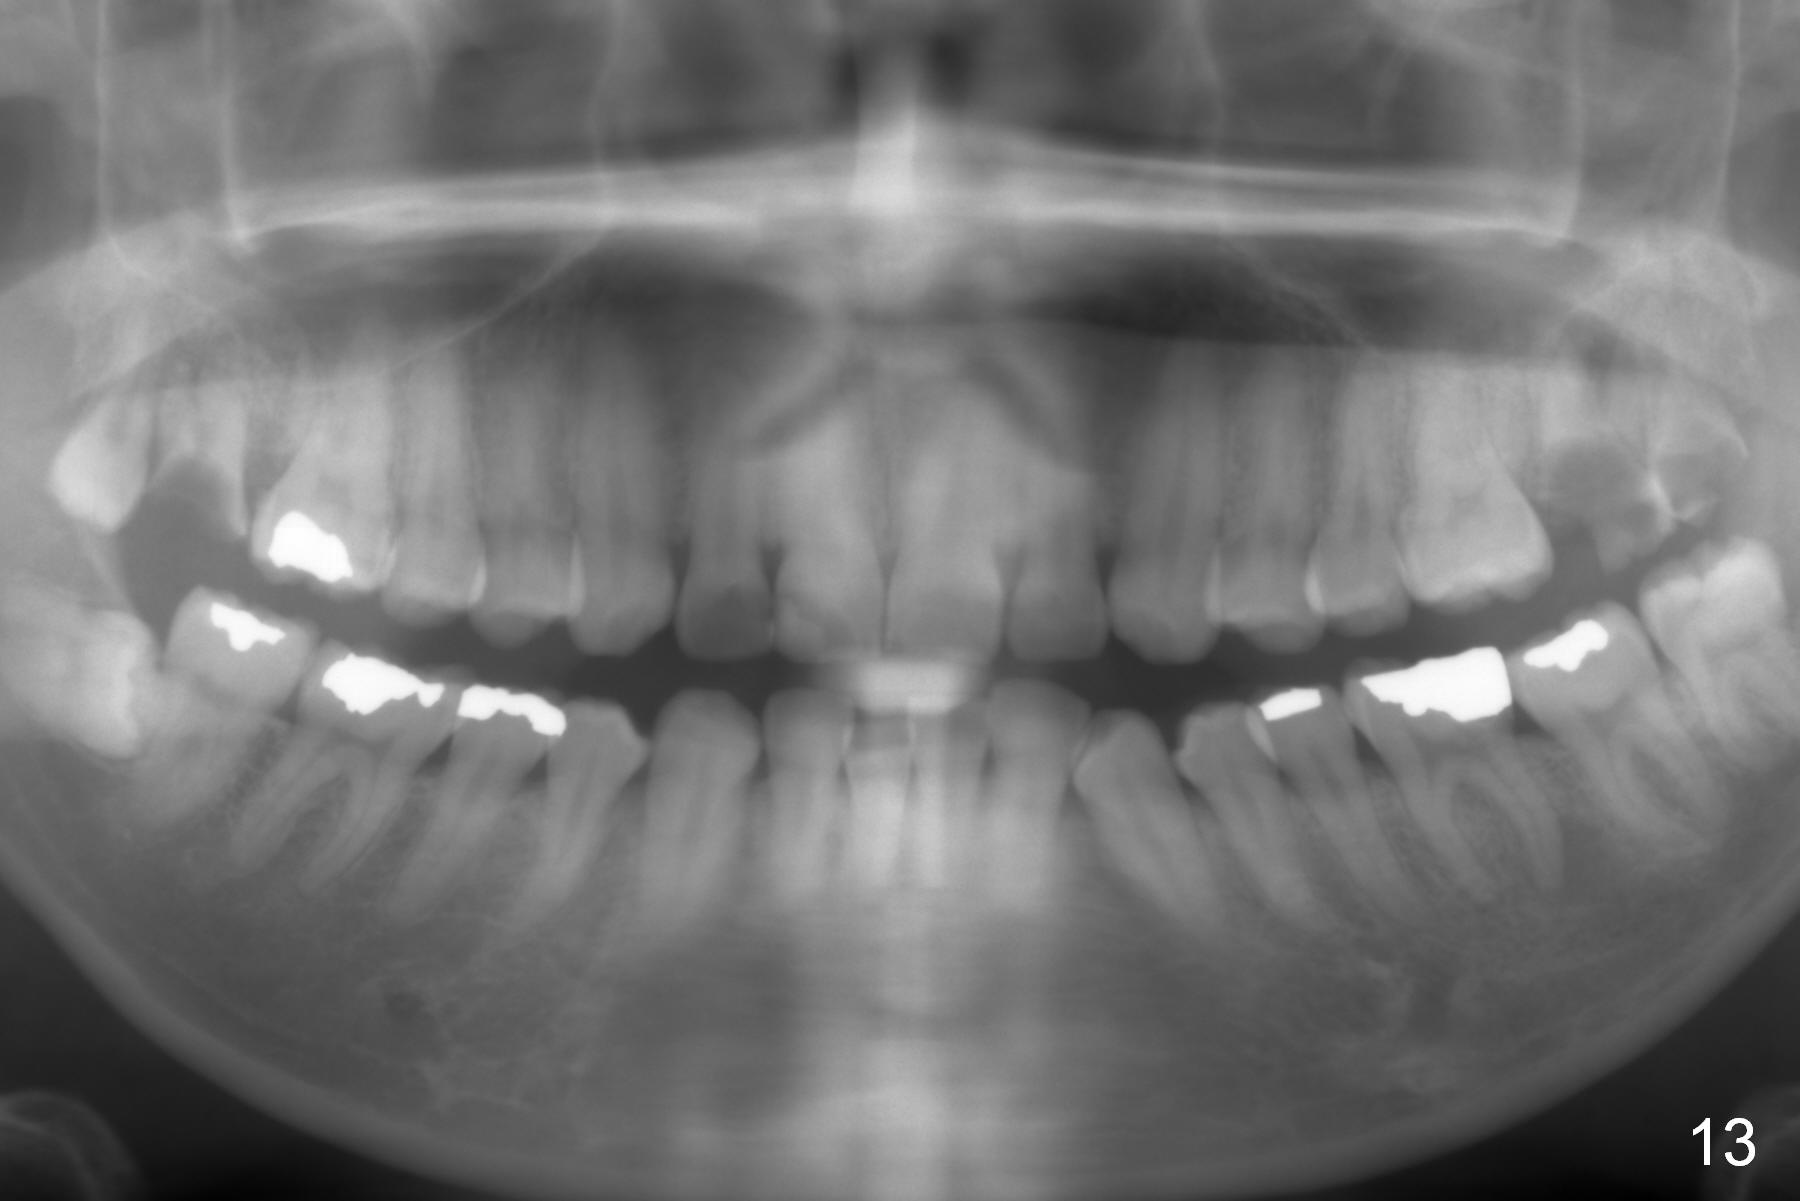

On March 9, 2016 (11.5 months of treatment), periodontal abscess develops around UR6 (Fig.11 (palatal view) *). It appears that the molar band as well as the buccal tube (Fig.12 *) is embedded into the gingiva. One week after band removal (as well as posted wire and closed coil springs), the infection resolves (Fig.14). As compared to preop Panoramus (Fig.13), the upper arch distalization is mainly at the crown level (Fig.4 arrows). The miniimplants should be placed higher (at the zygomatic arch); the post should be taller. Therefore the roots can be distalized as well (click the link below).